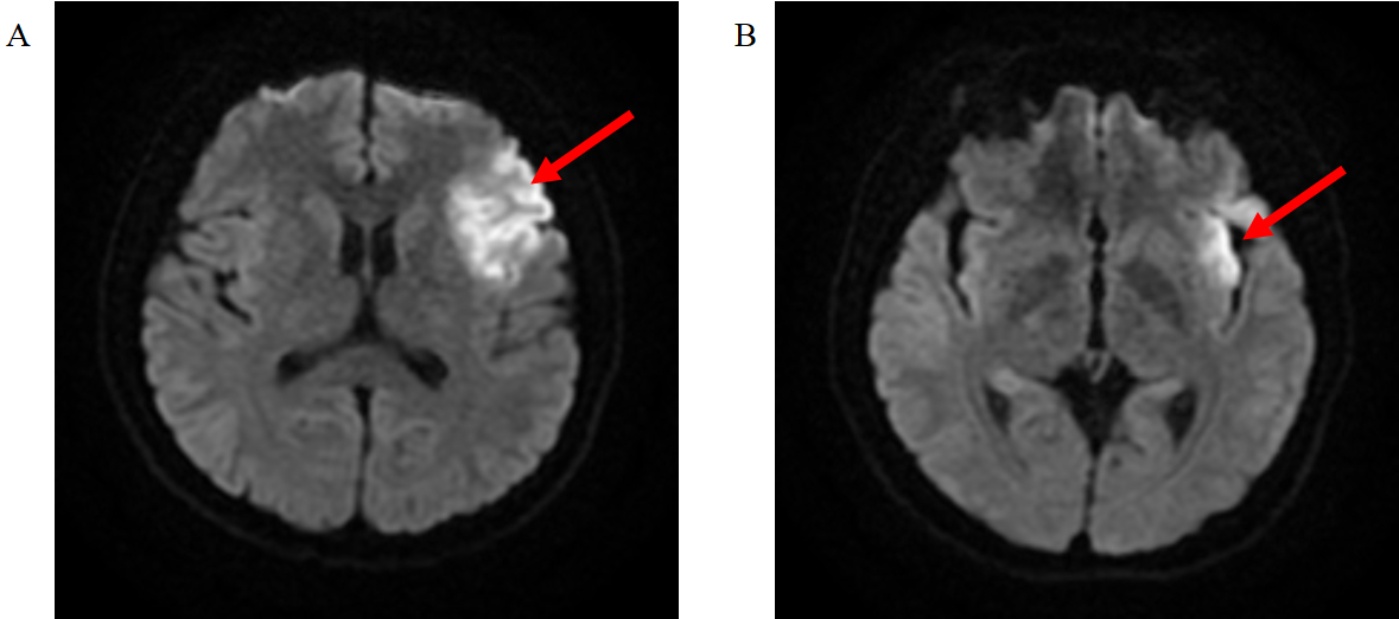

患者经抗PLA2R抗体阳性(100.05 RU/mL)确诊MN,依据KDIGO指南未行肾穿刺活检,予醋酸泼尼松30 mg qd + 环孢素软胶囊75 mg bid治疗,并辅以利伐沙班抗凝、硝苯地平 + 缬沙坦胶囊控制血压、阿法骨化醇软胶囊 + 碳酸钙D3片补钙等对症治疗。1个月后,患者出现手抖,醋酸泼尼松逐渐减量至20 mg qd;4个月后,患者出现牙龈增生、肿胀,复查24小时尿蛋白排泄量4.24 g/24小时(图1(A)),尿常规化学分析:隐血2+,尿蛋白3+。因患者应用醋酸泼尼松 + 环孢素副作用明显,且治疗效果差,遂再次入院评估RTX应用指征,完善化验示24小时尿蛋白排泄量6.08 g/24小时(图1(A)),PLA2R检测16.31 RU/ml (图1(L)),CD19+CD45+绝对计数及CD19 B细胞数均高于正常水平(图1(M)图1(N)),排除禁忌后于2024年9月22给予第一次RTX 600 mg治疗,输注过程顺利,无不良反应,准予出院,第一次RTX注射半月后,患者突发反应迟钝、站立不稳、言语重复,于我院急诊神经内科就诊,查体:记忆力、理解力、定向力、计算力下降,四肢肌力V级,肌张力正常,左侧共济运动欠稳准,双侧痛觉对称存在,四肢腱反射(++),NIHSS评分2分,饮水试验1级,ADL100分。完善颅脑MR示:左侧额叶、岛叶脑梗死(图2(A)图2(B)),右侧额叶深部、左侧小脑半球、斑片状异常信号影、考虑亚急性脑梗死可能性大;化验示抗心磷脂抗体(IgG + M + A):30.80 AU/mL (图1(O)),抗心磷脂抗体IgM:11.30 MPLu/mL (图1(P)),给予阿司匹林肠溶片100 mg qn、硫酸氢氯吡格雷片75mg qd、低分子量肝素钠注射液5000 IU皮下注射抗凝等治疗后好转出院,出院后规律应用华法林2.5 mg qd抗凝、阿托伐他汀钙片20 mg qn降脂。排除禁忌后,相继给予RTX 500 mg静脉滴注治疗3次,激素逐渐减停,2024年11月PLA2R及抗磷脂抗体转阴,2025年8月20日追加RTX 500 mg,(截至2025年8月20日累计应用RTX 2600 mg)。患者末次复查为2025年10月16日,并继续在门诊随访中。

Figure 2. Brain infarction cranial magnetic resonance imaging (DWI) images. (A) Frontal lobe cerebral infarction; (B) Insular lobe cerebral infarction

2. 脑梗死颅脑核磁共振(DWI)图像。(A) 额叶脑梗死;(B) 岛叶脑梗死